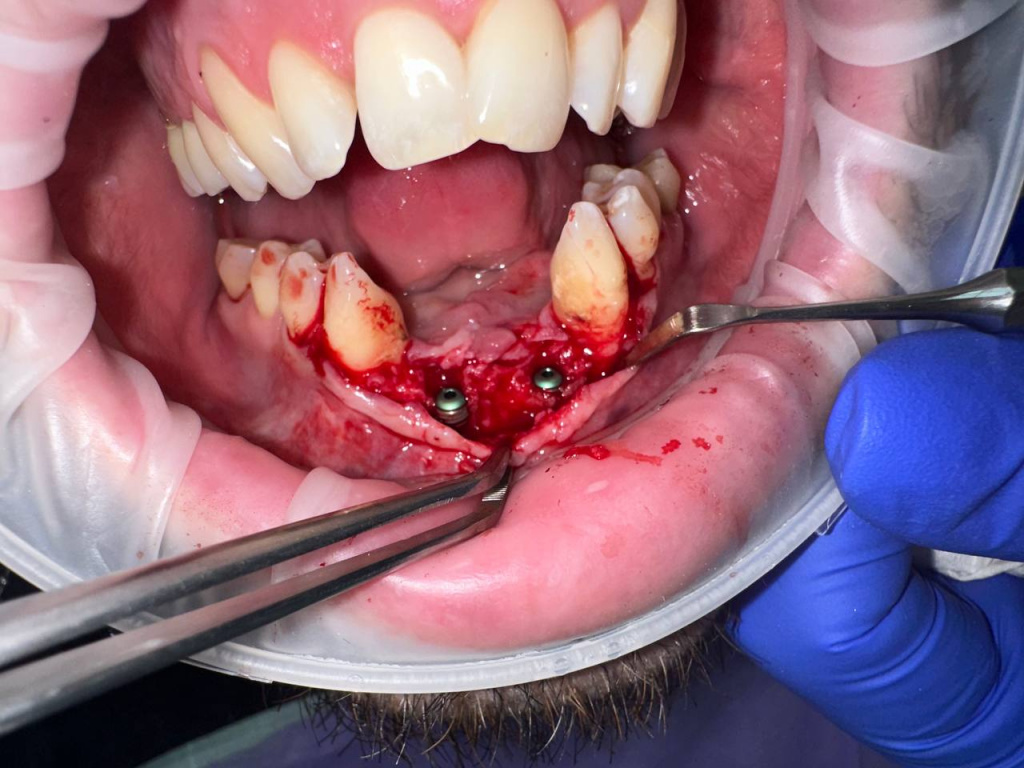

Уже много лет использую в своей практике имплантаты IMPRO. В этот раз мне предоставили линейку IMPRO Respect нового дизайна с широкими лепестками резьбы по отношению к телу имплантата. За счет чего получилось установить имплантаты в переднем отделе в узком гребне и с плохим костным предложением пациента. Ни разу не сталкивалась с осложнениями или проблем с имплантатми IMPRO Implantem. В этот раз не было исключением, была проведена операция через навигационный шаблон, имплантаты стабилизировались с хорошим торком. Хирургический набор и протоколы достаточно просты и удобны. Будем ждать ортопедической части, спустя месяц имплантаты стоят хорошо!

Пациент — мужчина 54 года.